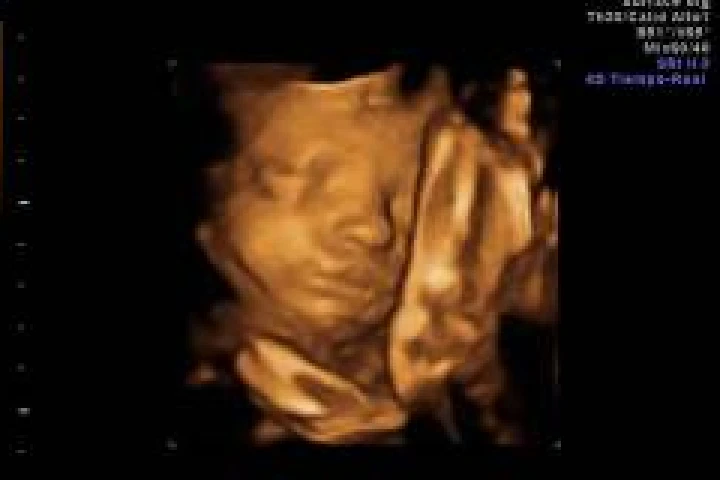

Bebés por nacer bostezan en el útero, revela estudio

foto Europa Press

Un equipo de investigadores de las universidades de Durham y Lancaster (Reino Unido) sugiere que los fetos bostezan dentro del útero, un proceso de desarrollo que podría dar a los médicos otro índice de salud.

Los investigadores analizaron las secuencias de vídeo 4D de 15 fetos sanos (ocho femeninos y siete masculinos) de entre 24 a 36 semanas de gestación para examinar de cerca todos los acontecimientos en un tramo de aftosa en el feto y hallaron que más de la mitad de las aberturas de la boca observadas fueron bostezos, según publica este miércoles la revista 'Plos One'.